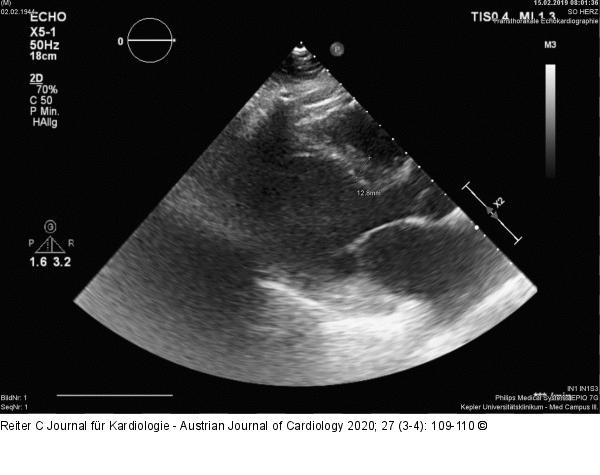

Abbildung 1: Echokardiographie Echokardiographie: Hypertrophierter linker Ventrikel bei einer interventrikulären Septumdicke von 13 Millimetern mit dilatiertem linkem Vorhof. |

Echokardiographie: Hypertrophierter linker Ventrikel bei einer interventrikulären Septumdicke von 13 Millimetern mit dilatiertem linkem Vorhof. |